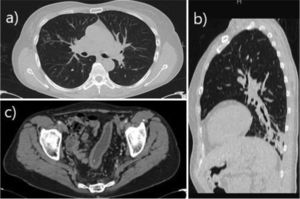

The patient was asymptomatic from a respiratory point of view until October 2017, when she began to experience cough and expectoration. High-resolution chest computed tomography (CT) revealed the presence of cylindrical bronchiectasis in the left lower lobe (Fig. 1). No potentially pathogenic microorganisms were isolated in sputum cultures. From a functional point of view, spirometry showed a moderate-to-severe obstructive pattern (FEV1 1.81 L [59%]; FVC 3.09 L [77%]; FEV1/FVC: 0.59). In January 2018, she was assessed at the bronchiectasis clinic: the patient reported purulent expectoration of approximately 40 cc per day and had required 4 courses of antibiotics since October 2017. Accordingly, treatment was started with inhaled bronchodilators (ipratropium bromide and salbutamol) and hypertonic saline 6% to facilitate expectoration of secretions. One month after treatment initiation (February 2018), due to the persistence of purulent expectoration—albeit to a lesser extent than prior to the use of hypertonic saline—nebulized ampicillin was added in order to keep the patient free from exacerbations.

(a) Axial CT slice in pulmonary window showing micronodular opacities with tree-in-bud distribution in the lateral segment of the middle lobe, consistent with infectious airway involvement. (b) Sagittal CT reconstruction in pulmonary window showing peripheral opacity of infectious appearance in the left lower lung associated with bronchiectasis. (c) Axial contrast-enhanced CT scan of the pelvis in soft tissue window, showing sigmoid colon wall thickening and submucosal edema of chronic appearance, related with the patient’s inflammatory bowel manifestation.